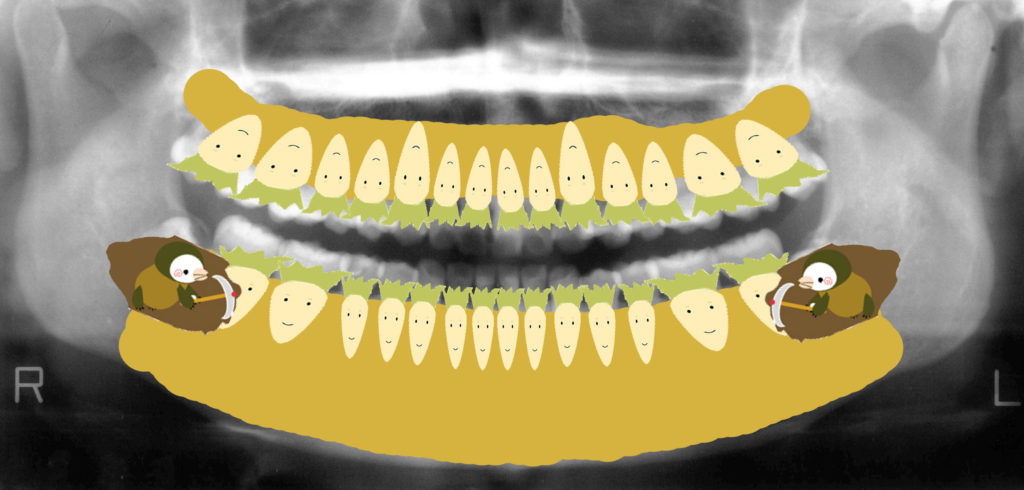

私は患者さんに説明するとき、よく「畑に大根が植わっているイメージ」とお伝えしています。

黄色い部分が畑(土=骨)、白い大根が歯です。

親知らずは隣の歯を圧迫し、どんどん食いつぶしていきます。

放置すると隣の歯もダメージを受けるのです。

畑(骨)に大根(歯)が植わっているイメージ

このレントゲン図をイラストにしてみました。

私はよく患者さんにお話しする時「畑に大根が植わっていると考えて下さい」とお伝えしています。

黄色い部分は畑(骨)です。

白い大根は(歯)です。

下顎の左右に生えていた親知らずは一生懸命大根を食いつぶしていっていますよね。

放置しておくと、どんどんどんどん隣の歯をくいつぶしていってしまいます。